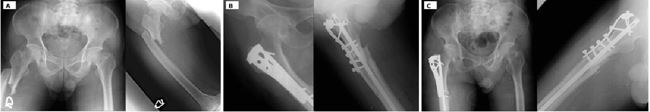

Case 1 – Shear-prone proximal femoral nonunion after intramedullary nailing

A patient with a proximal femoral fracture initially underwent IM nailing. Alignment and length were restored, but the construct left a long oblique fracture line at the metaphyseal–diaphyseal junction with a relatively wide canal–nail mismatch. Clinically, the patient reported persistent pain and difficulty weight-bearing; radiographs demonstrated hypertrophic callus with an unbridged lateral cortex and subtle toggling of the proximal fragment, consistent with a shear?dominated gap environment.

Revision surgery consisted of adding a short non-locking 3.5-mm dynamic compression plate through a limited lateral approach, spanning the fracture with two bicortical screws per segment. No nail exchange was performed. The plate was positioned to neutralize shear and rotational drift rather than to create absolute compression. At follow? up, radiographs showed progressive bridging of the lateral cortex and maturation of callus, and the patient regained functional weight-bearing with pain relief (Figure 4). Post- operatively, the Radiographic Union Score for Hip (RUSH) improved to 10 at 6 months, and the Visual Analog Scale (VAS) for pain decreased from 8 pre-op to 1.

https://www.jscimedcentral.com/public/assets/images/uploads/image-1770360023-1.JPG

Figure 4 Case 1—shear-prone proximal femoral nonunion after intramedullary nailing. Pre- and post-augmentation radiographs illustrate how adding a short lateral plate converts a shear?dominated gap into a consolidating construct.

Case 2 – Post-polio femoral hypertrophic nonunion

A poliomyelitis?affected limb with long?standing muscular imbalance sustained a femoral shaft fracture. Initial fixation using a lateral plate with cerclage wiring failed; plate breakage occurred under cyclical loading with loss of alignment and progression to hypertrophic nonunion. Radiographs demonstrated exuberant callus but persistent lucency at the fracture site and mechanical instability.

Revision treatment consisted of inserting an IM nail to restore axial alignment and length, combined with a short non-locking lateral plate acting as an anti-shear buttress over the nonunion site. The plate was deliberately kept short, with a limited number of bicortical screws, to avoid converting the system into an overly rigid load?bearing construct. Following revision, the patient progressed to radiographic union with gradual consolidation of the fracture line and improved function (Figure 5). The RUST score progressed from 4 at revision to 11 at final follow-up.

https://www.jscimedcentral.com/public/assets/images/uploads/image-1770360098-1.JPG

Figure 5 Vector-specific shear-shielding strategies in complex femoral phenotypes.

(Upper panel) Case 2: Post-polio hypertrophic nonunion. Standalone plating failed by fatigue fracture, consistent with persistent cyclic shear. Revision with an intramedullary nail plus a short lateral buttress plate preferentially reduced transverse motion (Δy) while preserving axial load sharing (Δx), enabling progressive consolidation.

(Lower panel) Case 3: Infra-isthmal distal femoral fracture. (A) Antegrade IM nailing in a distal-third, canal-widened segment with unfavorable nail–canal match, predisposed to bending/rotational micromotion. (B) Addition of a very short, non-locking lateral plate as a distal buttress to neutralize shear/torsion while maintaining axial dynamization, supporting consolidation on follow-up.